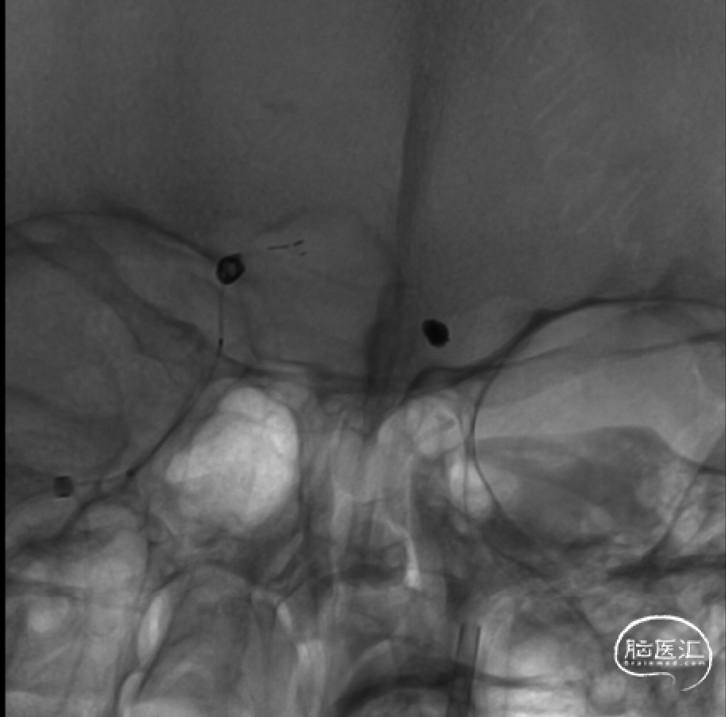

双侧椎动脉造影

压颈造影及压颈3D

1.左侧大脑前动脉A1起始部未破裂动脉瘤(囊性)

2.右侧大脑前动脉A1起始部未破裂动脉瘤(夹层)